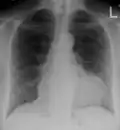

- Ultrasounds showing a pericardial effusion in someone with pericarditis

- A pericardial effusion as seen on CXR in someone with pericarditis